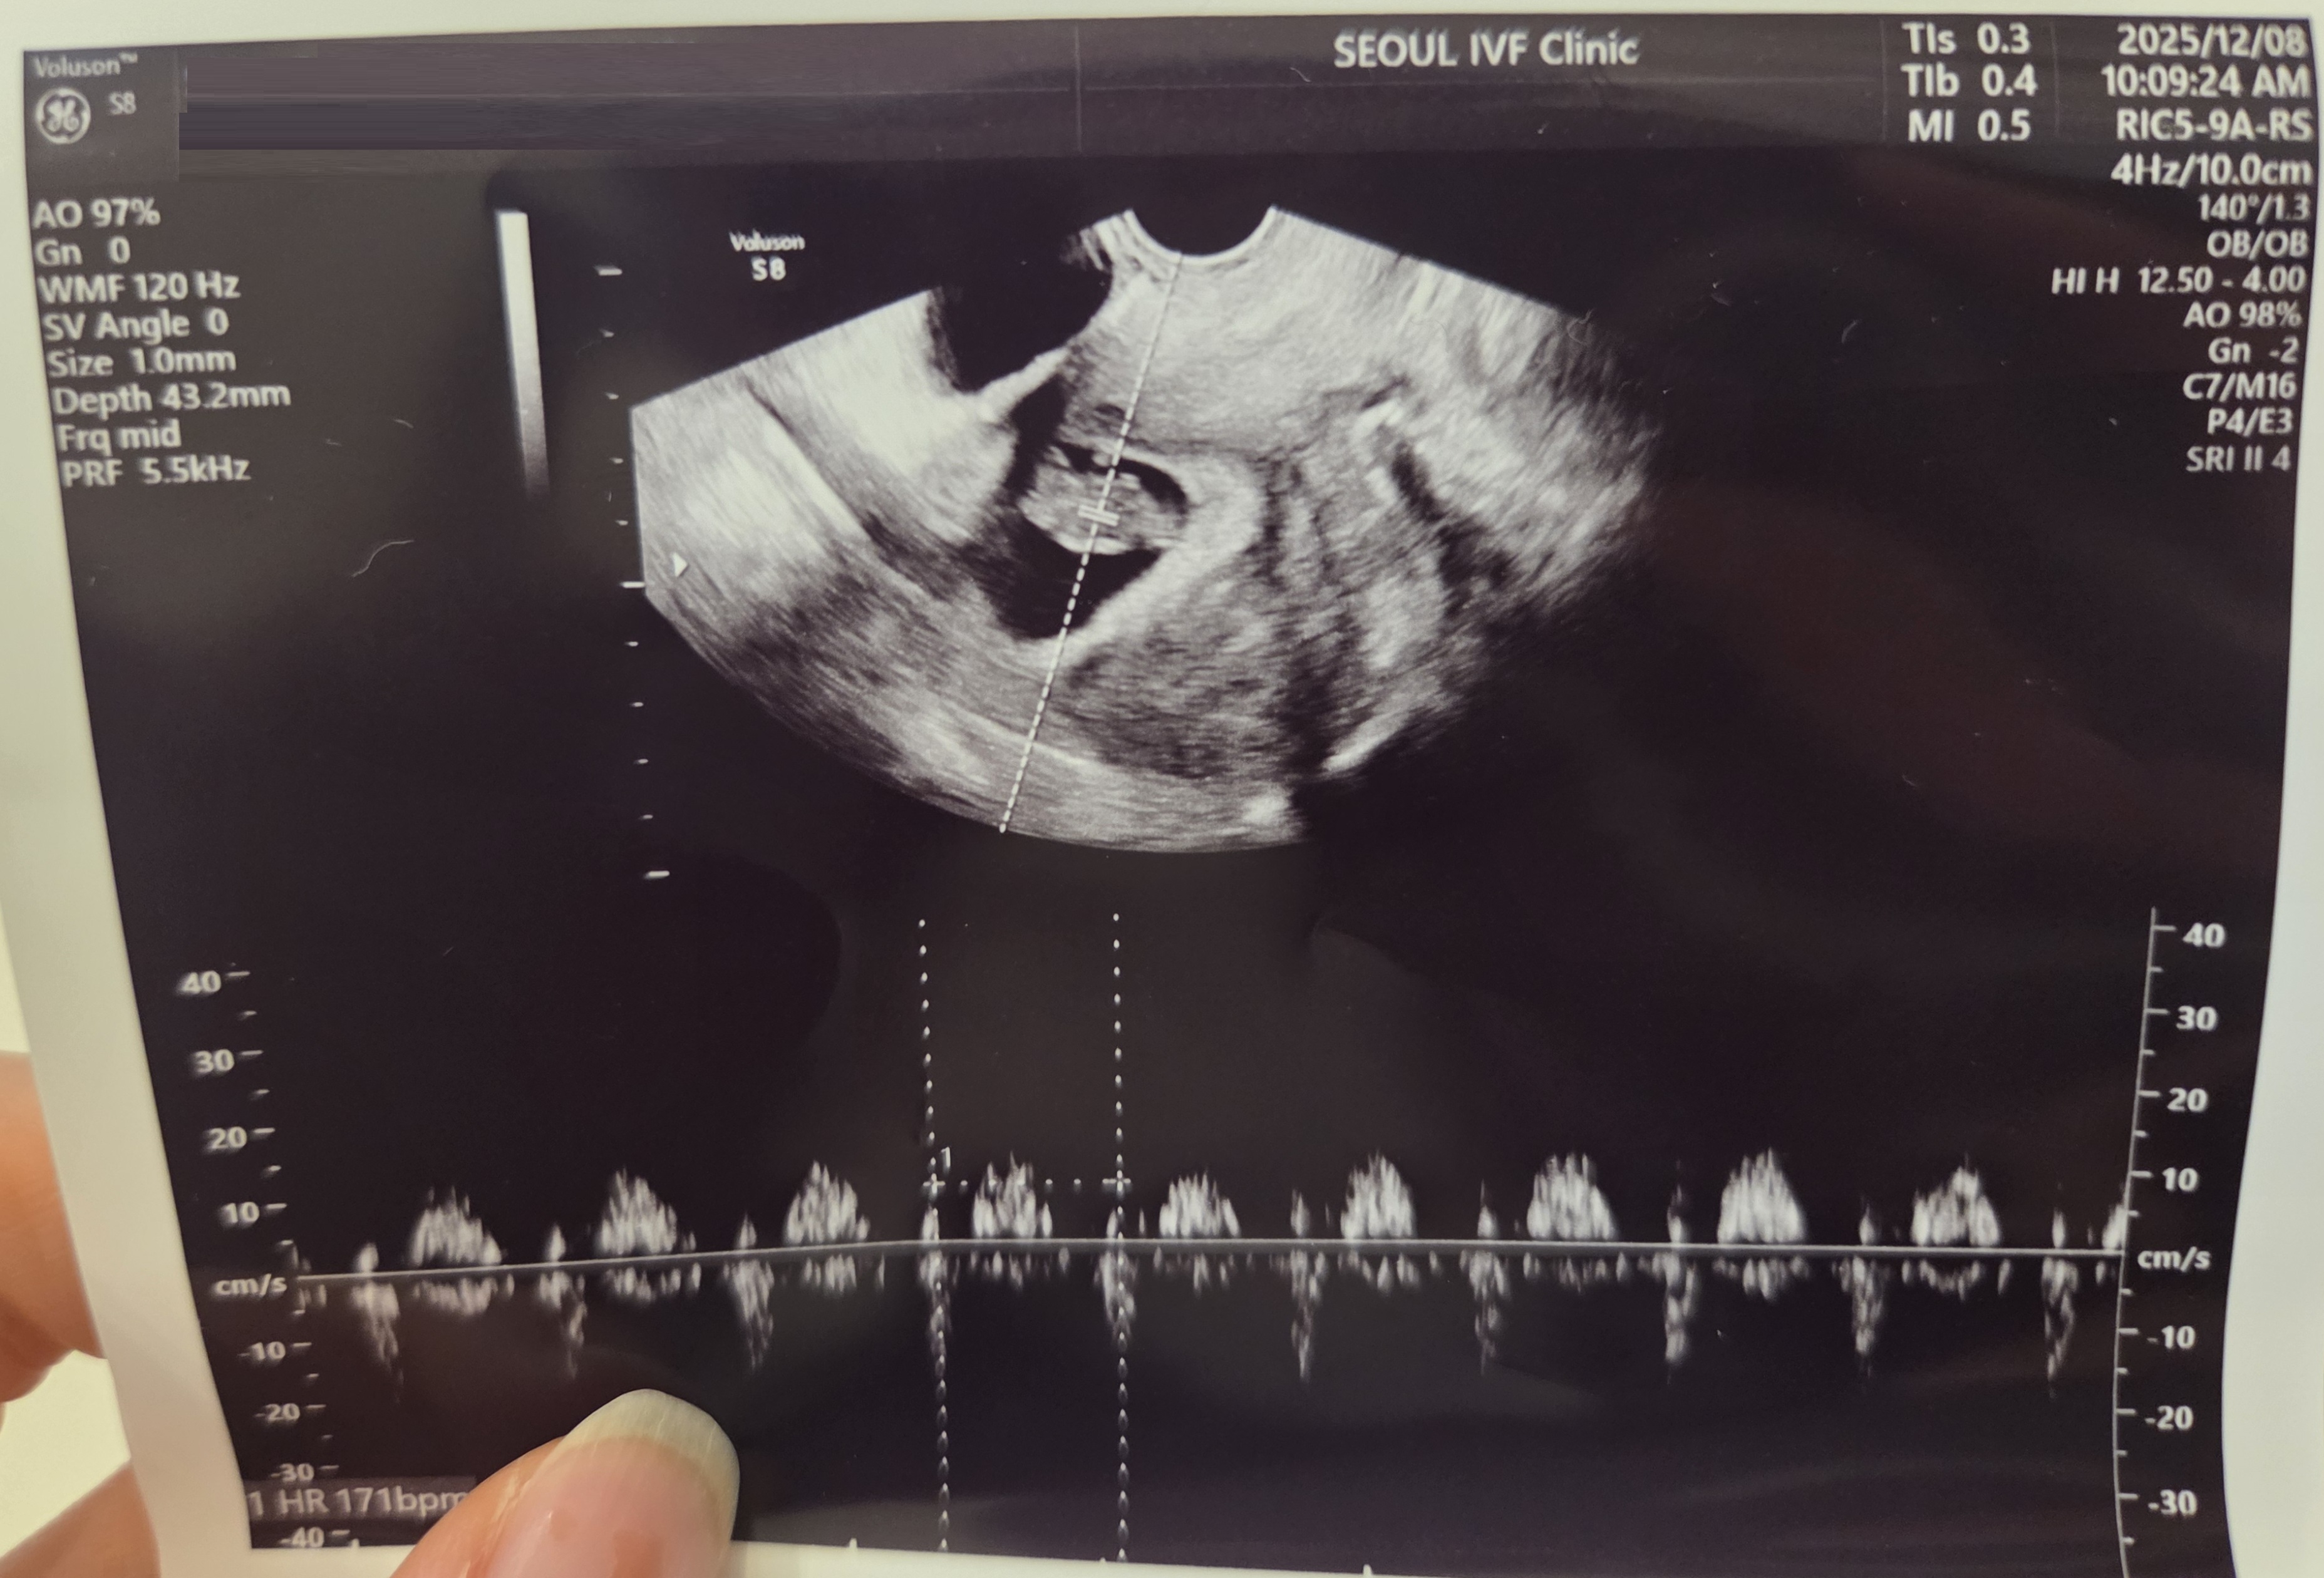

| 가슴 떨리는 임신 이야기를 공유해 주세요. | 처음 다니던 병원에서 1년 동안 시험관 시술만 네 차례 진행했지만 좋은 소식을 듣지 못했습니다. 이번이 정말 마지막이라는 마음으로 지금의 서울아이비에프를 찾았고, 이경훈 원장님께 시술을 받으며 다시 용기와 희망을 얻을 수 있었습니다. 그리고 감사하게도 한 번에 쌍둥이라는 기적 같은 임신 소식을 듣게 되었습니다.. |

| 치료 도중 느꼈던 가장 기뻤던 순간과 절망적인 것들은 무엇인가요? 잊지 못할 경험이 있나요? | 가장 힘들었던 순간은 1년 동안 여러 번의 시도에도 결과가 좋지 않았을 때였습니다. 몸과 마음이 모두 지쳐 더 이상 희망을 가져도 될지 두려웠습니다. 반대로 가장 기뻤던 순간은 새로운 병원에서 처음으로 좋은 소식을 들었을 때입니다. 한 번에 두 아이를 품게 되었다는 이야기를 들은 날, 그리고 이경훈 원장님께서 저보다 더 기뻐하시며 박수를 쳐 주셨던 모습은 평생 잊지 못할 순간입니다. |